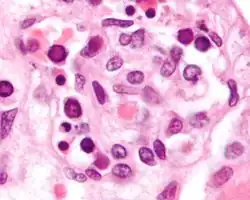

| 16-month-old with erythema infectiosum, displaying characteristic red rashes | |